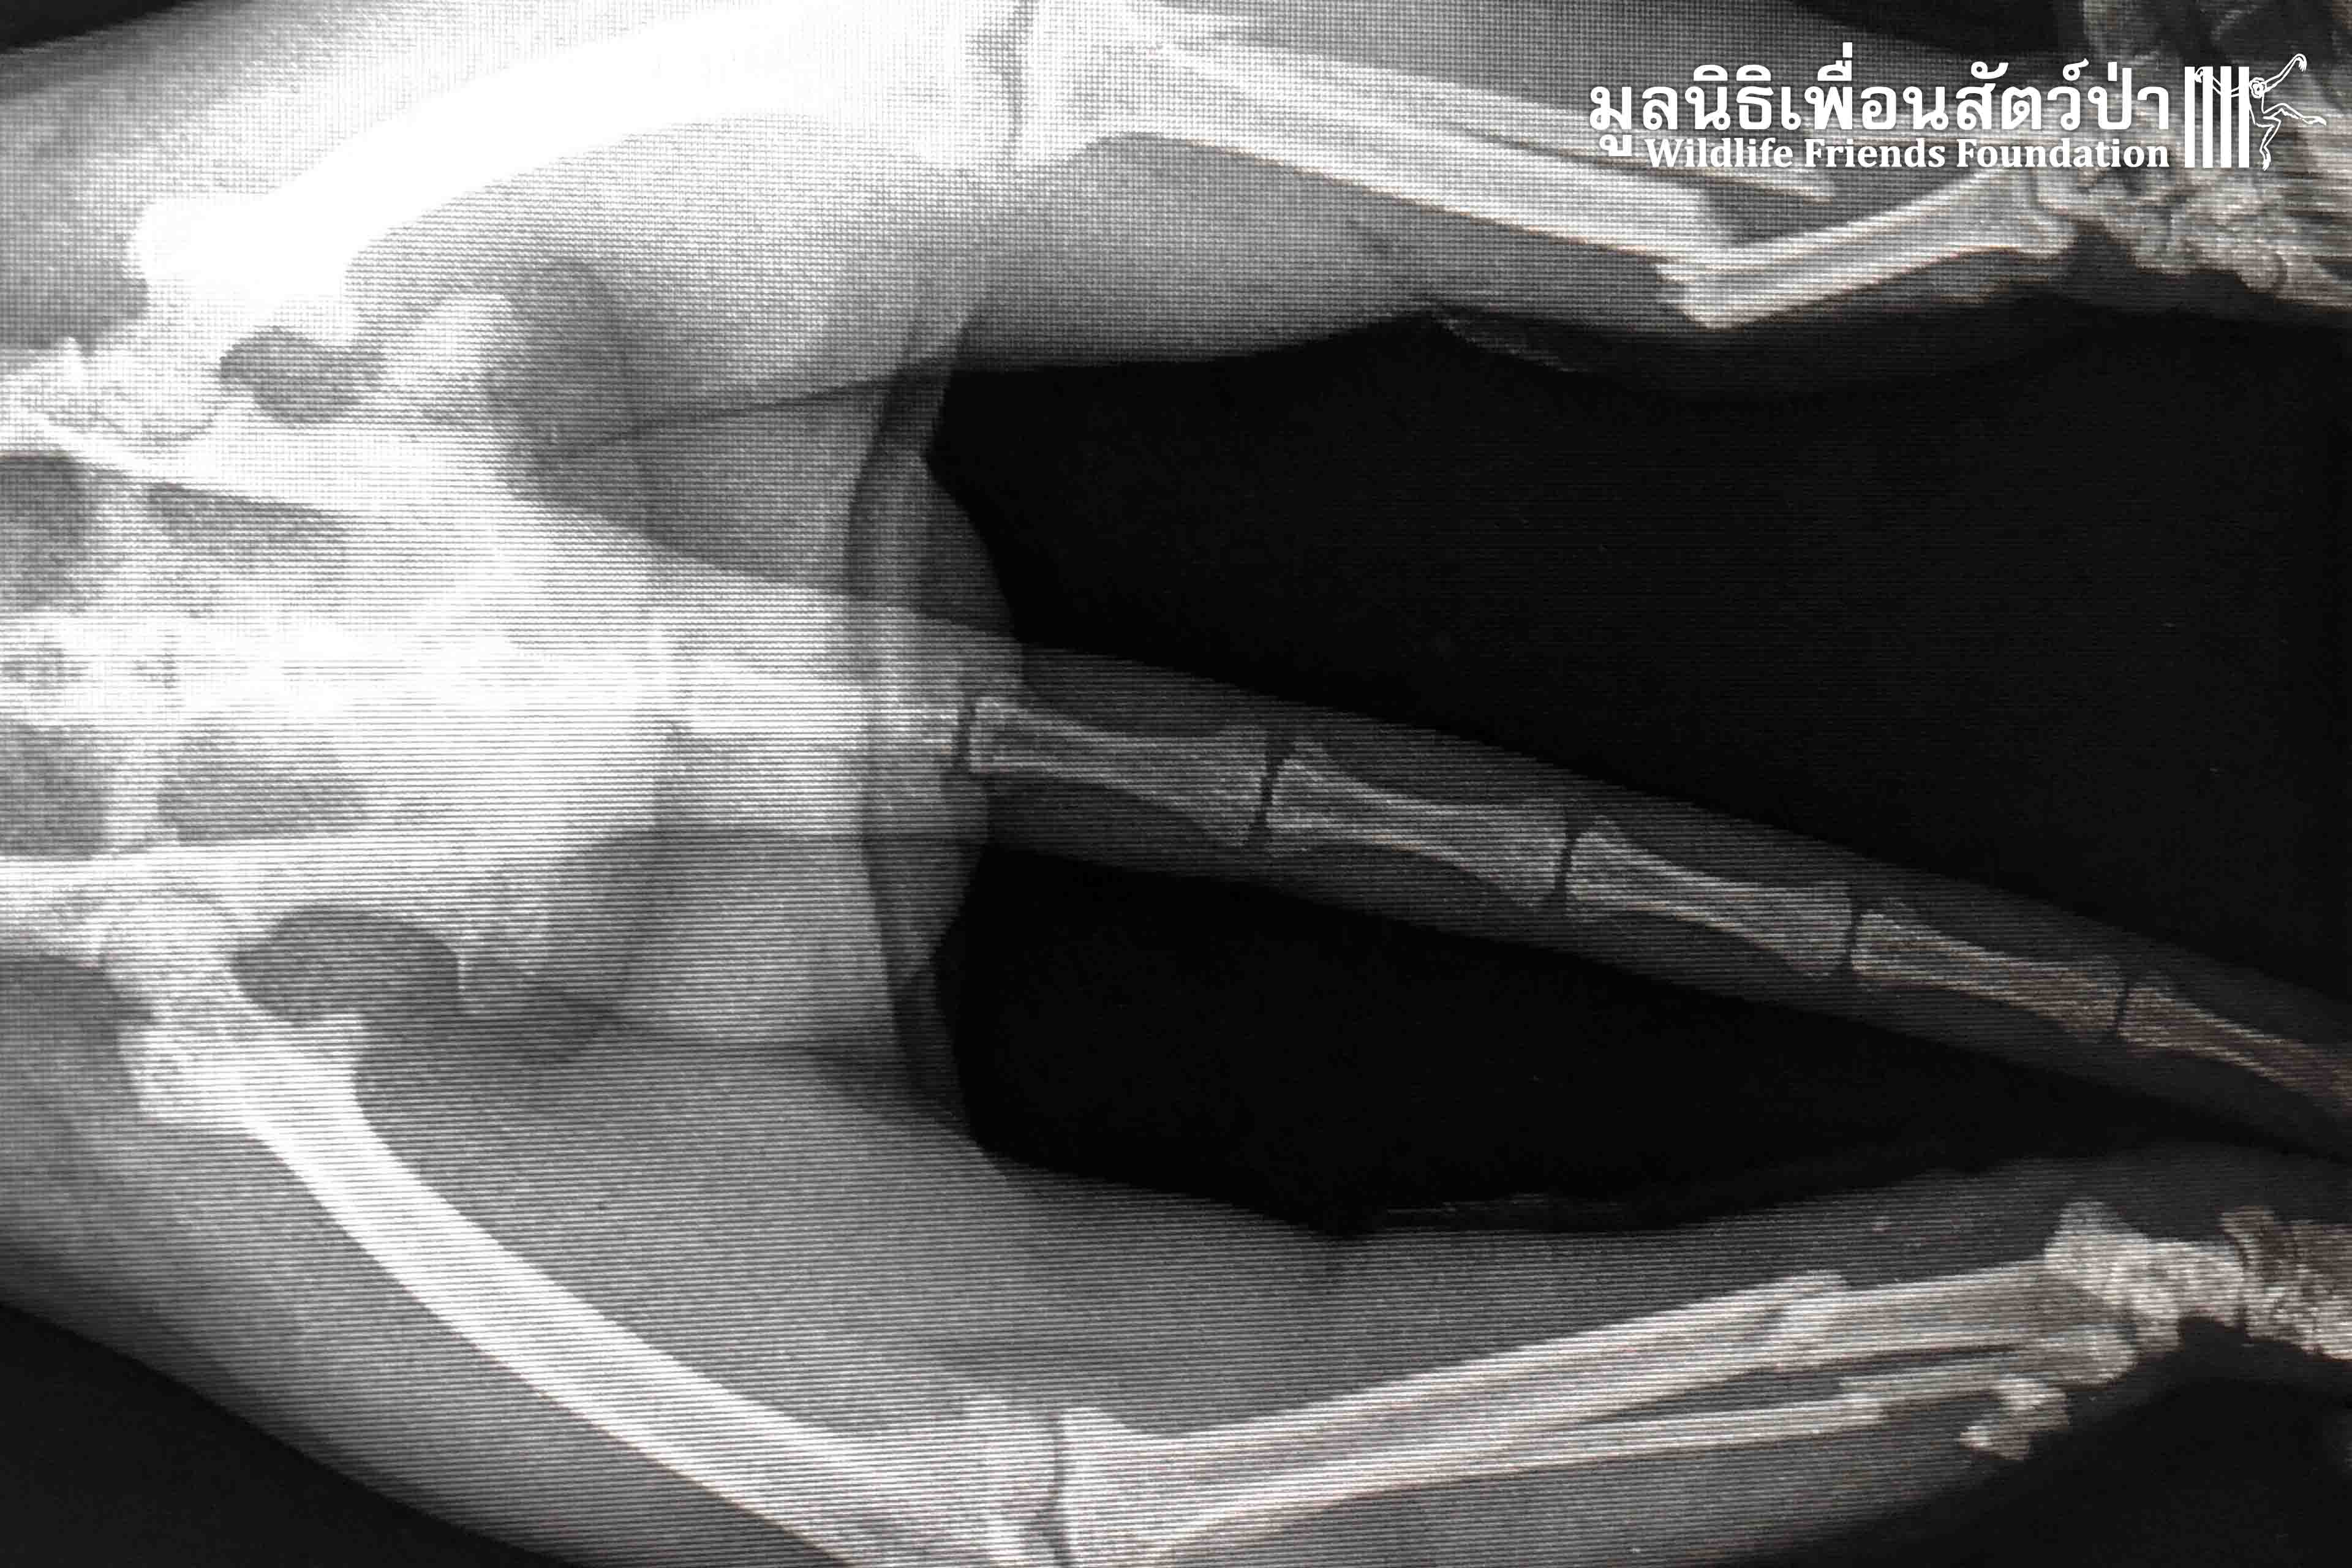

Bad luck for “Leggy” a male long tailed macaque (Macaca fascicularis), who fell 5 meters from a tree branch that unexpectedly broke. His bad luck didn’t end with bruises on his body… Leggy also sustained broken bones in both of his legs, preventing him from moving.

But sometimes bad luck brings good luck as well. A concerned local found Leggy immobile on the ground and contacted us about a monkey in need of emergency medical treatment. Now he is in the good hands of the WFFT vet team, where he will receive the care he needs until he recovers enough to be returned to the wild.